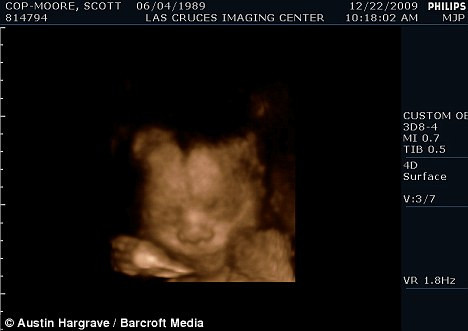

| Hình ảnh một bé trai trong bụng Scott sẽ mang tên Miles |

Scott, 30 tuổi, đã kết hôn hợp pháp với Thomas vì anh vẫn còn giấy khai sinh là nữ giới. Anh cho biết đang nóng lòng chờ đứa con tên là “Miles” ra đời.